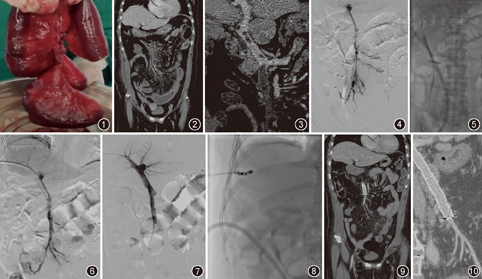

2014年1月至2016年1月南京市第一医院介入科接受介入治疗的8例急性PVMVT患者,发病时间1~12 d,男3例、女5例,年龄32~68岁,中位年龄52岁。1例为肠坏死切除术后(图1),3例为脾切除术后,1例肝硬化脾肿大,1例为胆囊切除术后,1例长期口服避孕药,1例实验室检查明确为S蛋白缺乏。8例患者介入治疗术前实验室检查、彩色多普勒超声及PV/SMV CTA(图2,图3)明确诊断(表1)。

患者平卧位,右侧胸壁消毒铺巾,根据术前CT图像确定穿刺点位置,在超声及DSA引导下用微穿刺针行右侧PV分支穿刺成功后,注入对比剂明确穿刺针头端位于PV右支远端分支,置入微导丝及扩张管,然后引入4F单弯导管,在泥鳅导丝配合下将导管远端植入SMV远端行PV/SMV造影(图4),明确血栓部位、程度。

置换入7 F鞘管及交换导丝,然后通过导丝置入Xpeedior血栓喷射抽吸导管。所有患者均在术中使用尿激酶25万U(溶解入100 ml生理盐水),通过喷射模式进行血栓内喷射溶栓。血栓内喷射灌注后,等待15 min,将AngioJet机械性血栓清除装置由喷射模式改变为抽吸模式进行血栓抽吸,灌注液体改为溶有普通肝素5 000 U的生理盐水500 ml(术前所有8例患者均排除了肝素诱导血小板减少综合征的诊断)。然后将抽吸导管沿着导丝以1 mm/s的速度进行血栓抽吸(图5)。抽吸术后即刻造影(图6),血栓清除评价标准[5]:血栓清除率>90%为Ⅲ级;血栓清除率50%~90%为Ⅱ级;血栓清除率<50%为Ⅰ级。2例血栓抽吸术后PV/MVT仍有明显毛糙,予球囊扩张后置入自膨支架。

除1例支架植入术后PV/SMV完全通畅(图7),而且考虑到患者7 d前行部分空肠切除术,予以立即拔管之外,7例患者均留置溶栓导管进行持续溶栓治疗,尿激酶用量50万U/d。24 h后造影复查,监测凝血时间,如果血栓完全溶解,则终止溶栓治疗;48 h再次造影复查,所有病例均终止溶栓治疗。终止治疗后拔除溶栓导管及鞘管,鞘管肝内段采用边退导管边进行肝内穿刺通道栓塞,直至肝脏包膜下,其中1例采用明胶海绵条栓塞,其余7例均采用纤毛弹簧圈栓塞(图8)。患者PMT术后1、7 d复查血常规、尿常规和肝肾功能,对比术前及术后白细胞、血红蛋白、丙氨酸转氨酶、天冬氨酸转氨酶、肌酐、尿素氮变化;术后1、6个月行PV/SMV CTA复查(图9,图10),所有患者随访6月,术后口服抗凝治疗至少6个月。

所有患者PV/SMV均进行了PMT治疗(表1),抽吸时间120~220(168±33)s。抽吸术后造影评估,评估PV/SMV血栓清除率3例Ⅲ级,5例Ⅱ级。其中2例予PV及SMV球囊扩张及支架植入治疗。持续溶栓时间0~48(30±16)h,尿激酶用量25~125(88±33)万U,终止溶栓后重新评估所有5例患者血栓清除为7例Ⅲ级,1例Ⅱ级。所有患者术后1个月及6个月时进行PV/SMV CTA随访均未见血栓复发,2例植入支架患者支架内血流通畅。